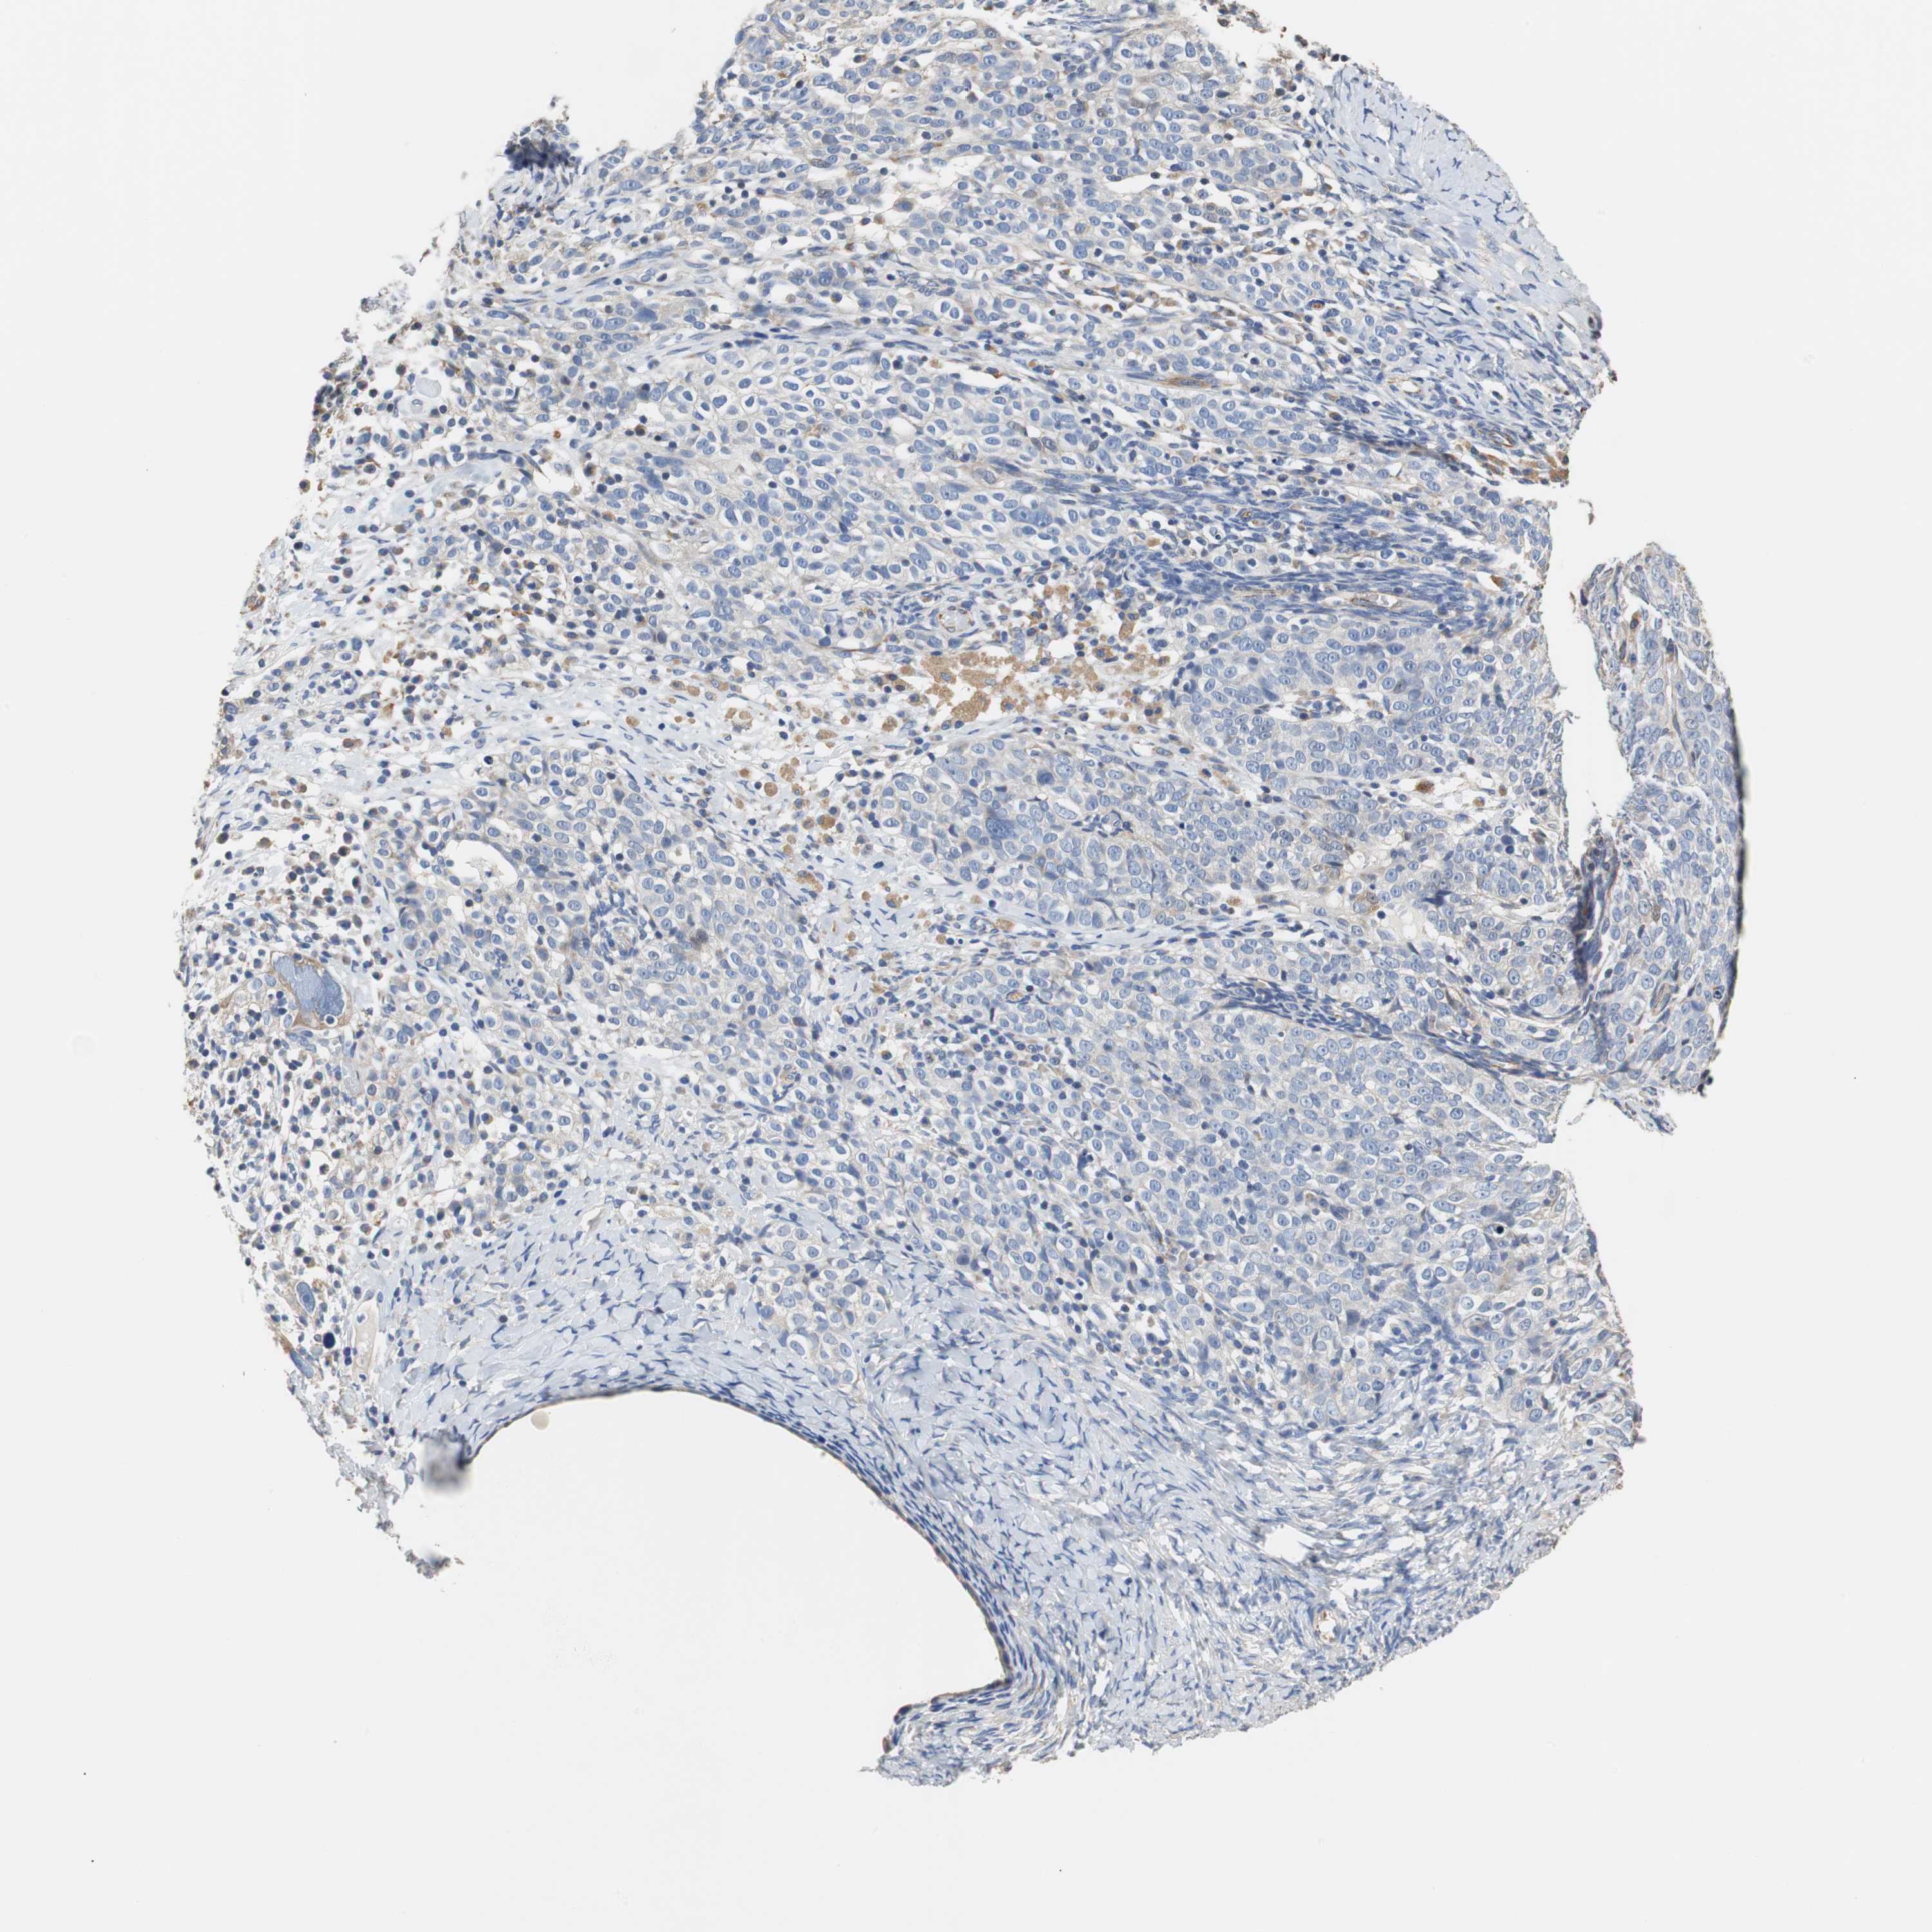

OVARIAN CANCER - Protein expressioni

A mouse-over function shows sample information and annotation data. Click on an image to view it in a full screen mode. Samples can be filtered based on level of antibody staining by selecting one or several of the following categories: high, medium, low and not detected. The assay and annotation is described here.

Note that samples used for immunohistochemistry by the Human Protein Atlas do not correspond to samples in the TCGA dataset.

Antibody stainingi

Antibody staining in the annotated cell types in the current human tissue is reported as not detected, low, medium, or high, based on conventional immunohistochemistry profiling in selected tissues. This score is based on the combination of the staining intensity and fraction of stained cells.

Each image is clickable and will lead to virtual microscopy that enables deeper exploration of all samples and also displays staining intensity scores, fraction scores and subcellular localization as well as patient and tissue information for each sample.

Antibody HPA006277

Cystadenocarcinoma, serous, NOS